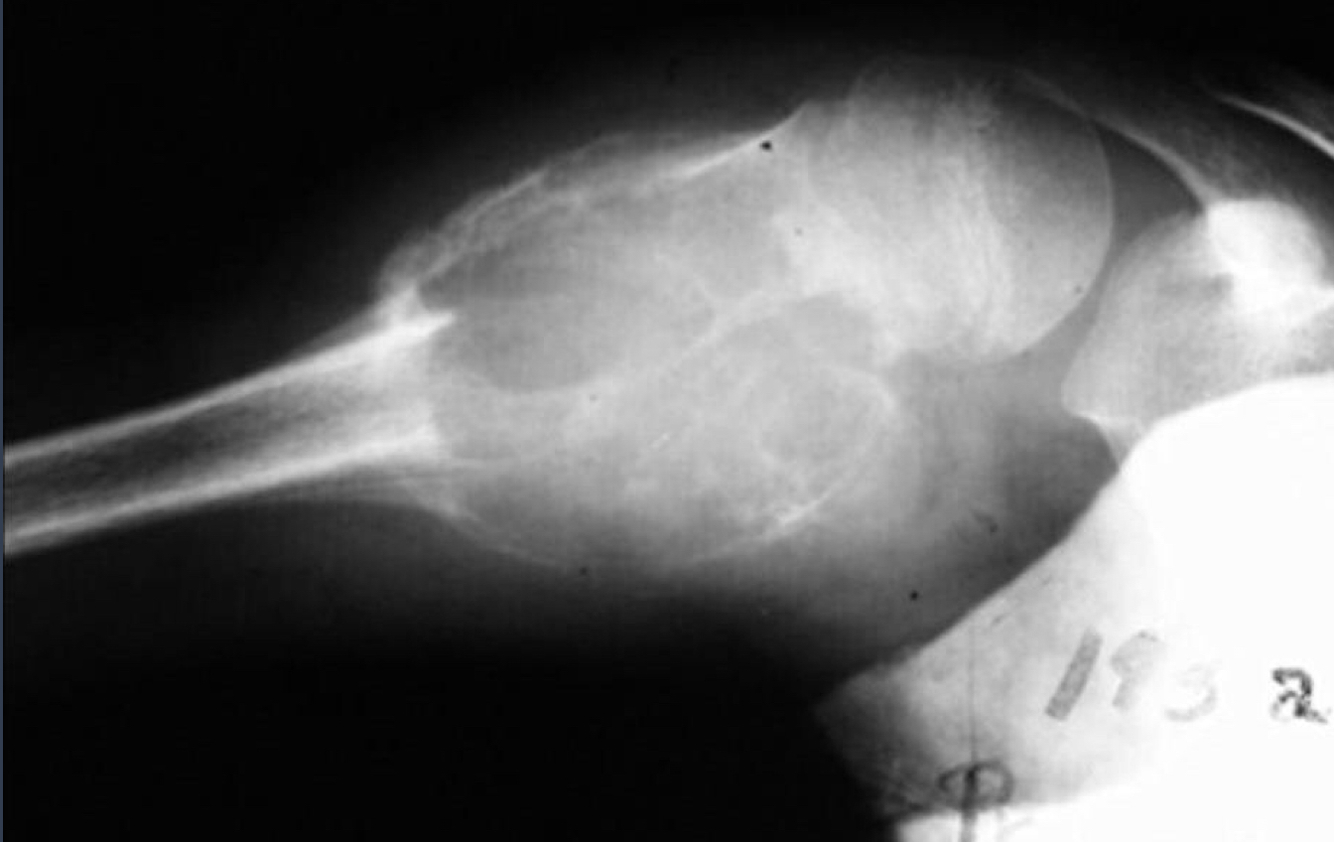

what is this?

ABC

describe this. what is this?

distal radius

extends into subchondral region

diminished bone density

appears aggressive

malignant GCT